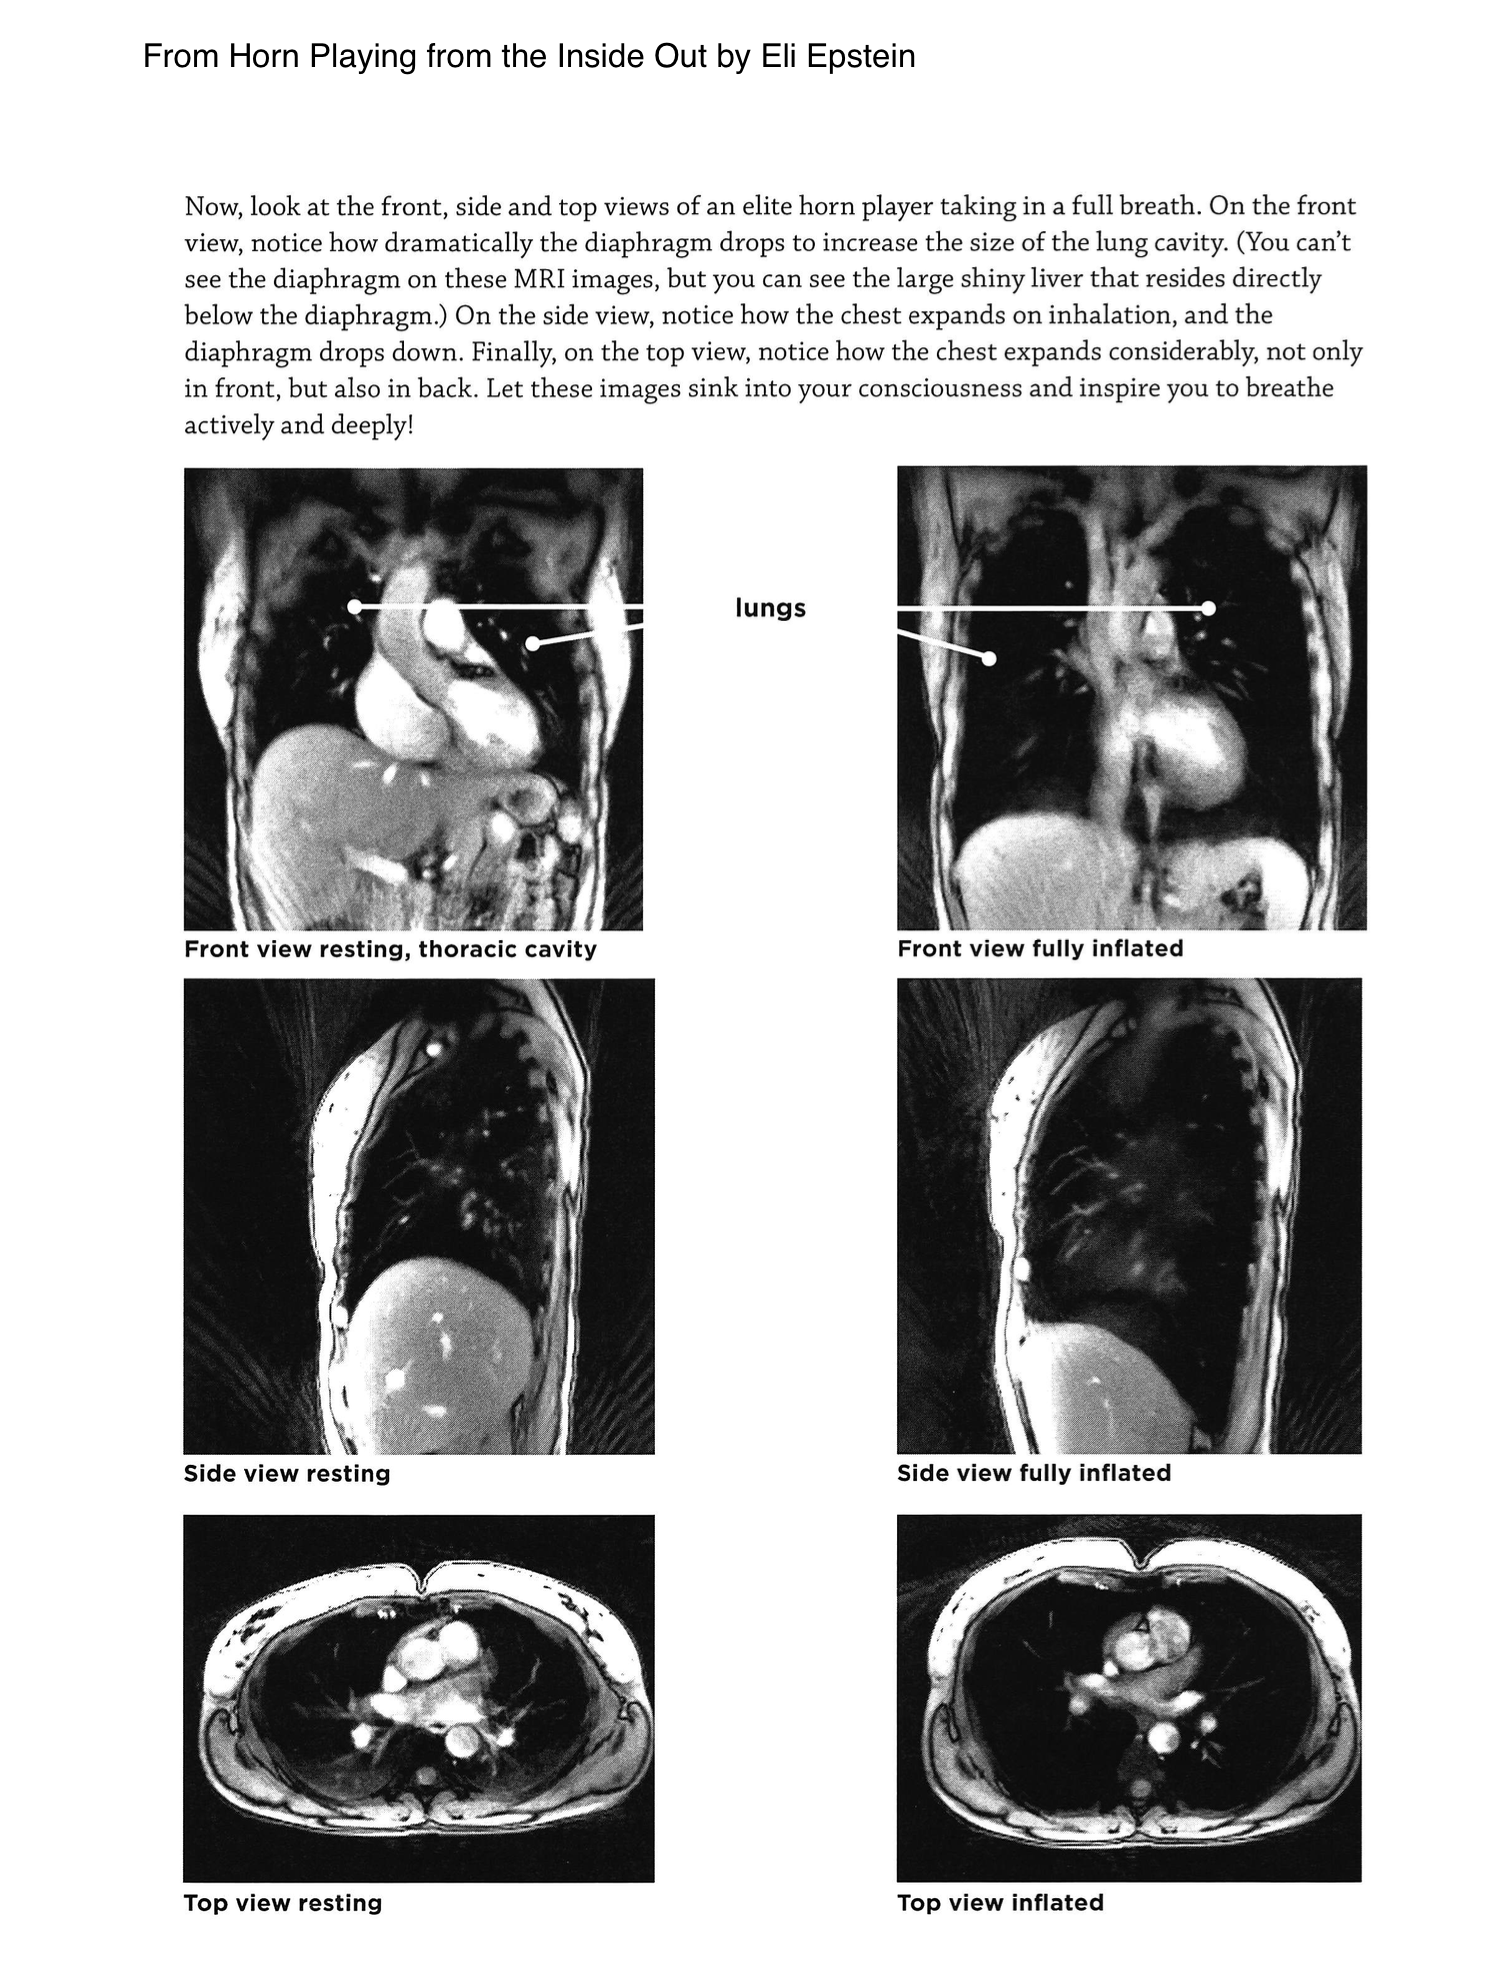

MRI views from Horn Playing from the Inside Out by Eli Epstein, showing front, side, and top views of a horn player's thoracic cavity at rest and fully inflated